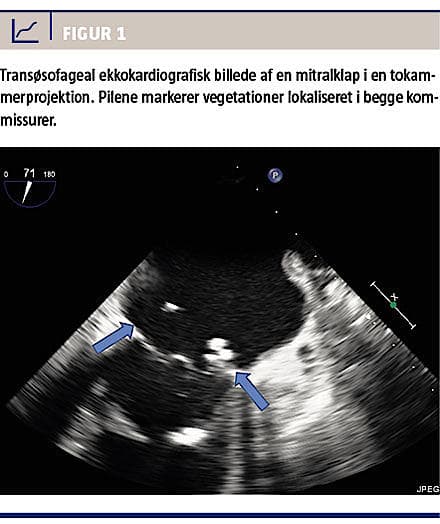

Ca. fire måneder efter første klapoperation blev patienten igen indlagt på lokalsygehuset med febrilia, tiltagende dyspnø, træthed og dårlig almentilstand. Man fandt her pneumoni og sternuminfektion med siven fra en fistel. Man fandt nu L. monocytogenes i tre ud af tre bloddyrkninger. Ved transøsofageal ekkokardiografi fandt man en velfungerende aortaklapprotese, men på en forkalket mitralklap var der to ekskrescenser i begge kommissurer – begge målte ca. 1 × 1 cm (Figur 1 og Figur 2). Der blev indledt behandling med meropenem og ciprofloxacin i endokarditisdosering, som bakterien senere blev fundet fuldt følsom for. Pga. svær almen svækkelse kompliceret med bl.a. fornyet gastrointestinal blødning, svampeinfektion og gradvis yderligere reduceret lungefunktion vurderedes det, at patienten var inoperabel, og han afgik efter kort tid ved døden efter tre af i alt seks ugers antibiotisk behandling. Efterfølgende viste den identificerede L. monocytogenes sig ved helgenom sekventering, og deraf udledt multilocussekvenstype, at være samme type som udbrudstammen, nemlig ST-224, der var identificeret i den pågående nationale epidemi udgående fra en fødevarevirksomhed.